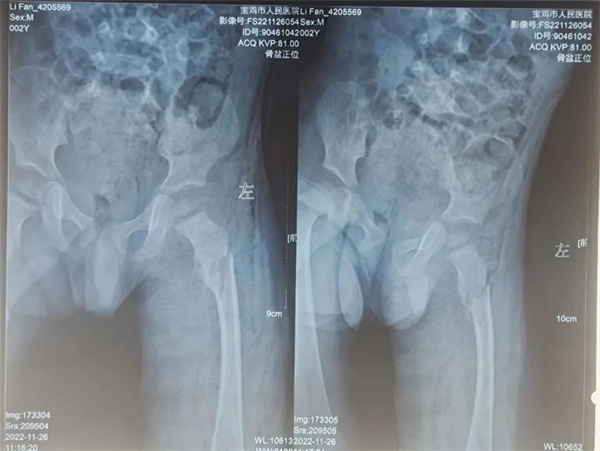

两岁的帆帆因为在家中玩耍时不慎踩空从楼梯上摔落,孩子哭闹不止,父亲发现孩子大腿明显肿胀,遂来市人民医院急诊科就诊。急诊科为其进行X线检查显示 “左股骨粗隆下骨折、断端错位明显”,建议患儿住院行进一步专科治疗,遂患儿转入骨一科。

刚受伤时照片